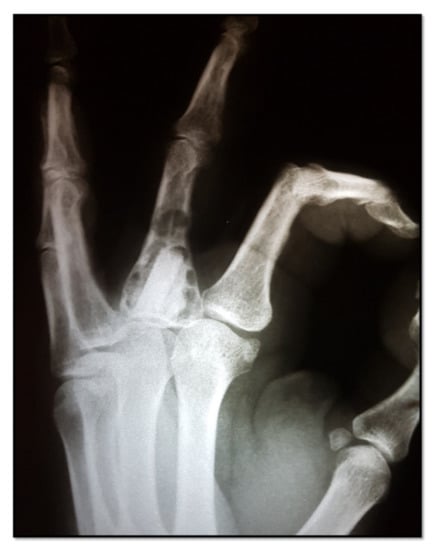

Our report included 15 patients, 11 men and 4 women, aged between 30 and 68. The patients were admitted and underwent surgery in the Plastic and Reconstructive Surgery Department of the “Sf. Spiridon” Emergency Clinical Hospital Iasi, as well as in the Orthopedics and Traumatology Department of the Vaslui Emergency Clinical Hospital between January 2016 and December 2018. The follow-up period was at least 2 years for each case. All the patients gave their consent for surgery and participation in this study. An agreement from the Ethics Committee of the Hospital was obtained. All cases were diagnosed with solitary enchondroma, and we did not include patients with multiple sites of enchondroma in this study. The suspicion of enchondroma was raised by plain radiographic findings and clinical examination of the hand, and the diagnosis was confirmed by histopathology. Nine of the patients included in this report presented without symptoms. In these cases, the tumor was found accidentally on an X-ray taken for another reason. Three patients presented to the hospital for pain or swelling. In the other three cases, the first sign was a pathologic bone fracture. The fracture occurred during daily activities in the absence of trauma. All cases from this study had surgical indications due to the large volume of the tumor, affecting more than 50% of the cortical circumference. The surgical procedure consisted of curettage of the tumor cavity followed by filling or natural healing. In 9 of the 15 cases, the procedure was performed under regional anesthesia with a bloodless operative field by exsanguination and the use of a pneumatic tourniquet. The other six cases were performed under local anesthesia using the WALANT technique (Wide Awake Local Anesthesia No Tourniquet), using a solution of 1% Lidocaine with Epinephrine in a concentration of 1:100,000 [17]. After curettage, all the resected tissue was sent for anatomopathological examination and diagnosis establishment. In cases in which the tumor was located in the distal phalanx, after curettage, the cavity was left to heal naturally, and the finger required immobilization for 3 weeks in a plastic splint for middle phalanx, distal interphalangeal joint and distal phalanx in full extension (Figure 1).

Figure 1. Enchondroma of the distal phalanx. (A)—radiological finding of enchondroma of the distal phalanx; (B)—excision of enchondroma using a surgical scoop; (C)—Excised tumor; (D)—bone defect after tumor excision, left for natural healing.